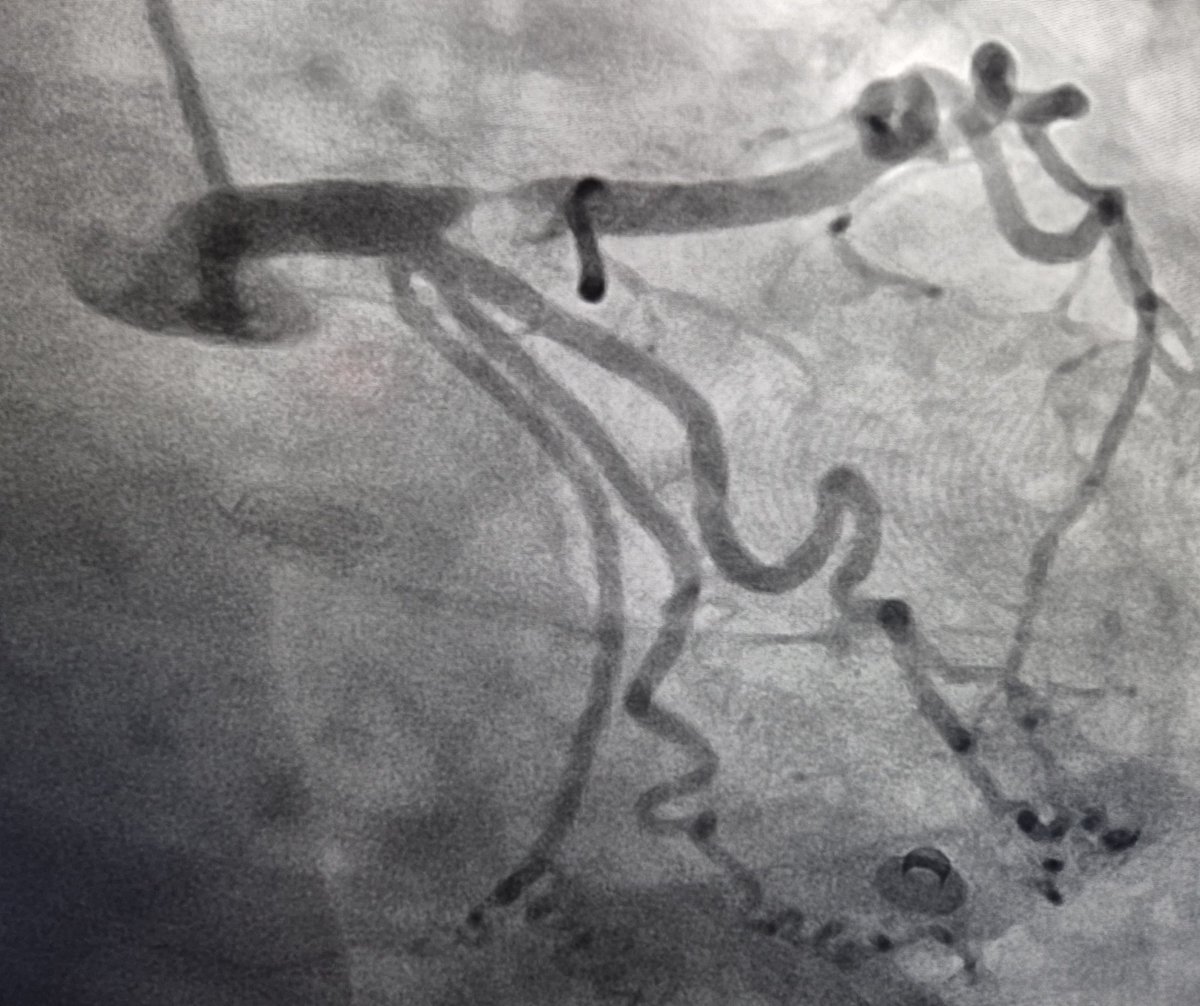

A 63 y.o female presented with NSTEMI. One year before CTA with normal LAD/RCA and mild lesion in OM1. Here is the angio and OCT images. What would you do?